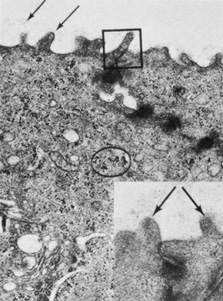

As the midstromal fibers travel toward the central cornea, axons become finer, and beaded features are seen along the filaments prior to their termination. Collaterals from the midstromal fibers branch anteriorly at 90 degrees to create an extensive sub-Bowman's layer plexus. Fibers from the plexus travel anteriorly through Bowman's layer toward the epithelium, where they again turn at 90 degrees and travel parallel to the corneal surface just posterior to the epithelium. Based on confocal microscopy, the majority of fibers in the subbasal plexus of the central cornea appear to be oriented along the superior-inferior axis. There are approximately 5400 to 7200 nerve bundles in the subbasal plexus; because each bundle may contain several axons, the total number of axonal fibers may be as high as 44,000.105 Each fiber immediately forms numerous, elaborate leashes with up to several dozen beaded axon terminals per leash and some additional unbeaded fibers. The beaded appearance was at one time considered an artifact of tissue processing or trauma; however, confocal microscopy has shown these to be genuine features (Fig. 24). The unbeaded straight terminals are not seen entering the epithelium; however, the beaded terminals of the leashes diverge vertically and obliquely among the epithelial cells in a complex manner before terminating at the level of the apical cells (Fig. 25).102 The diameter of the individual nerve fibers in the subbasal plexus are between 0.05 and 2.5 μm with most being in the range of 0.1 to 0.5 μm.

Fig. 25. Nerve axons (N) are visible in the basal cell layer of the epithelium (49,500×). (Courtesy of Drs. Rodrigues, Waring, Hackett, and Donohoo.)